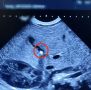

В Балаковской городской клинической больнице зафиксировали клинической случай: у 1,5-месячного ребенка диагностировали холецистит и камни в желчном пузыре.

Малыш поступил с желтушкой и плохой прибавкой в весе. Обследование показало: виной всему — небольшой камень, частично перекрывший желчный проток.